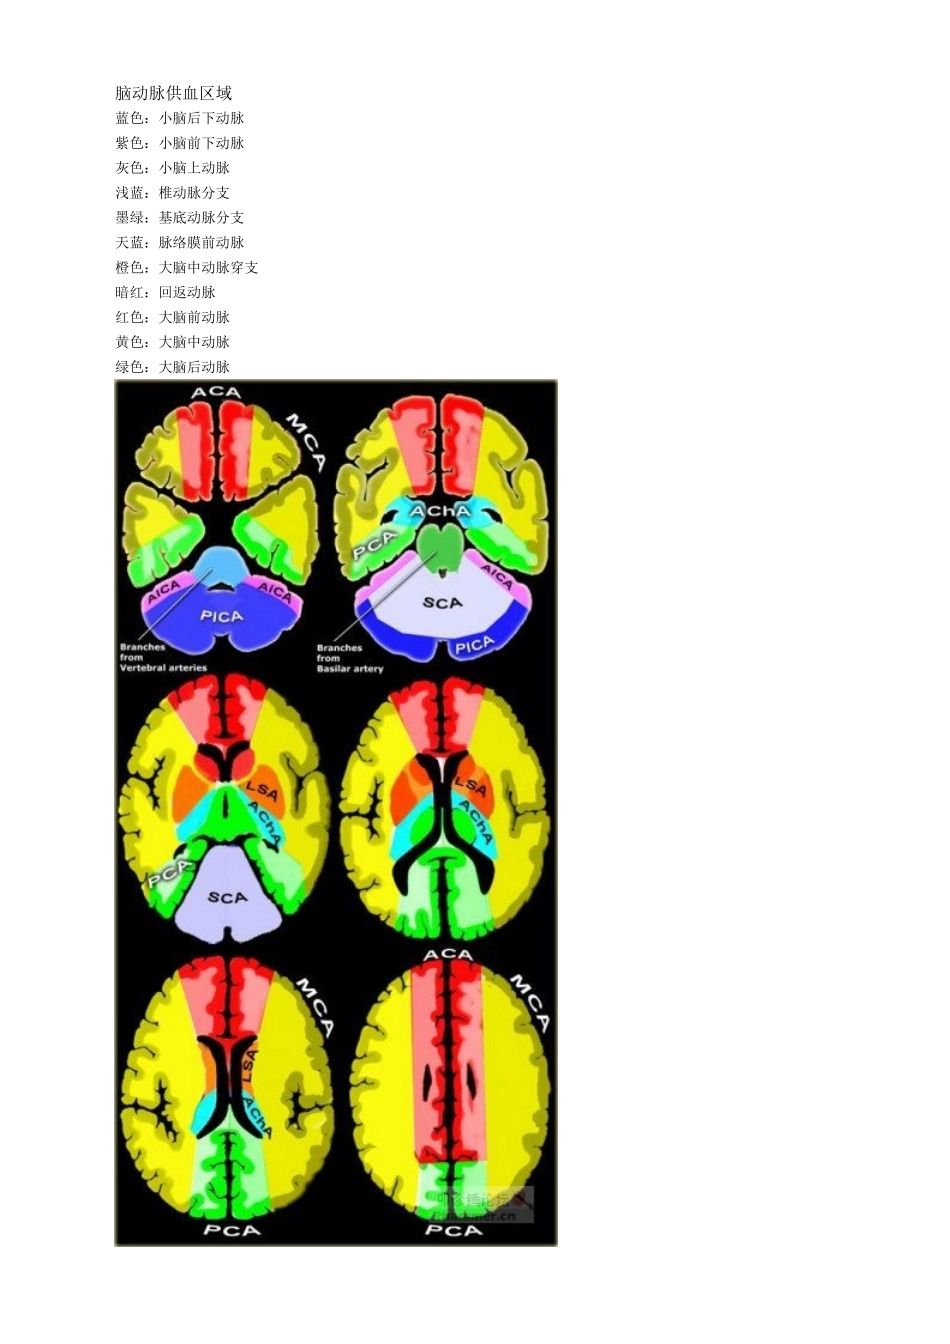

脑动脉供血区域蓝色:小脑后下动脉紫色:小脑前下动脉灰色:小脑上动脉浅蓝:椎动脉分支墨绿:基底动脉分支天蓝:脉络膜前动脉橙色:大脑中动脉穿支暗红:回返动脉红色:大脑前动脉黄色:大脑中动脉绿色:大脑后动脉